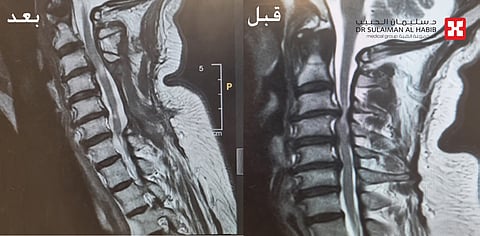

وقد كشفت النتائج بدقة عن وجود ضغط شديد ومتزايد على الحبل الشوكي بالفقرات العنقية في الرقبة، وبناءاً على المعطيات والنتائج قرر الفريق الطبي المعالج التدخل الجراحي العاجل، وذلك لإنقاذ الحبل الشوكي من الاعتلال والحد من إصابته بمزيد من المضاعفات، حيث تم تحضير المريض وتجهيز غرفة العمليات بطاولة متخصصة لمثل هذه الحالات تعرف باسم "Jackson Table" ، والتي توفر للفريق الطبي القدرة على دوران المريض في أي اتجاه وقت العملية، وكذلك توفير جهاز " Mayfield" الذي يساعد في دقة النتائج وتثبيت الرأس أثناء الجراحة.

موضحاً أن العملية الجراحية استغرقت 5 ساعات متواصلة تحت التخدير العام، وتم فيها عمل فتح جراحي والوصول لمنطقة الفقرات العنقية، ومن ثم إزالة الضغط الشديد على الحبل الشوكي باستخدام المايكروسكوب الجراحي ، نقل بعدها المريض لجناح التنويم، حيث تلقى رعاية طبية فائقة على مدار يومين، وقد استطاع الوقوف والمشي بأريحية تامة وانتهت لديه نوبات الألم وتنميل الأطراف، وخرج بعدها من المستشفى وهو بصحة ممتازة ولله الحمد.